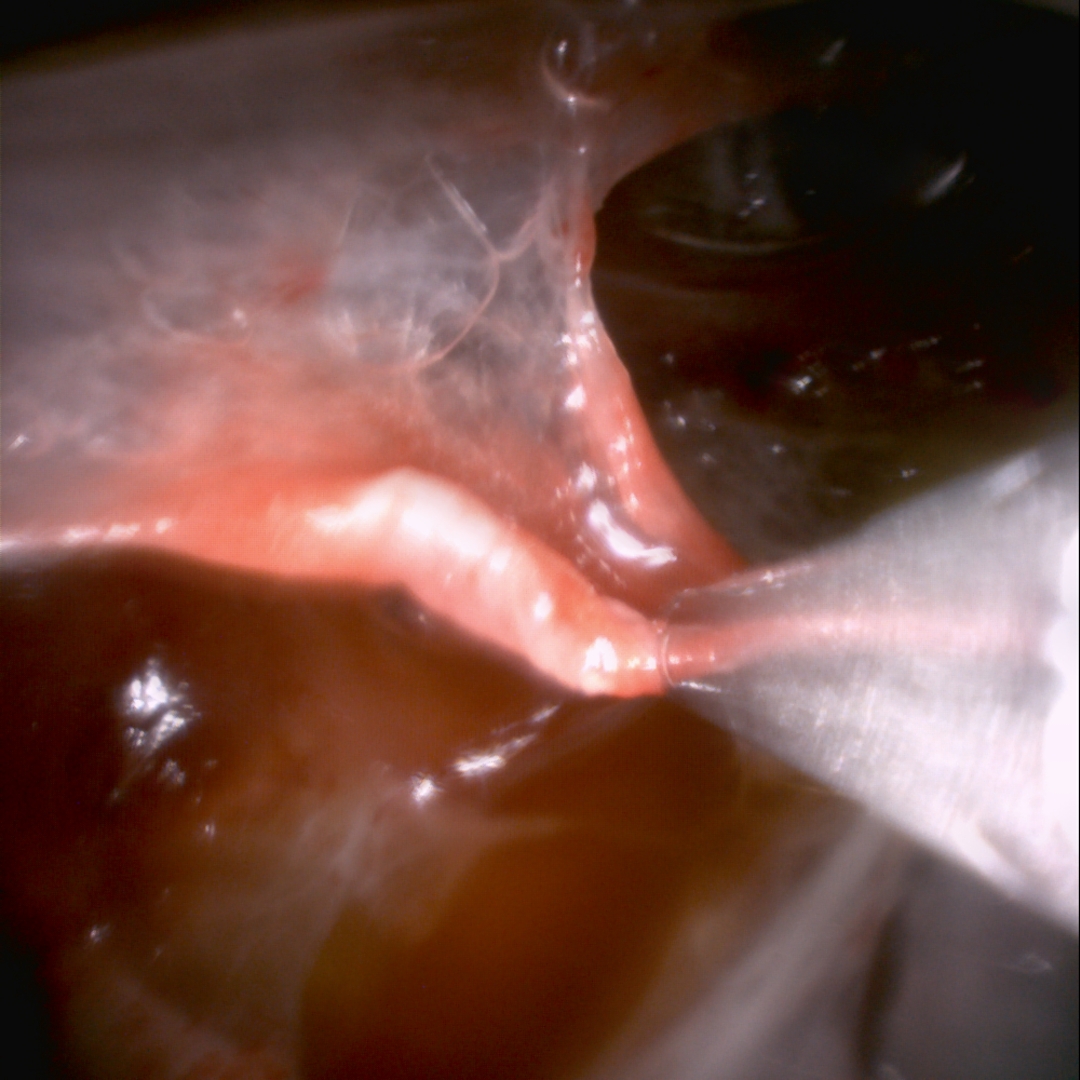

检查前团队提前完成了全套准备工作:由总院专家远程指导梳理诊疗流程,对高清内镜系统、监护设备等进行反复调试,并联合胸外科、麻醉科及重症医学科等多学科制定详尽的应急预案,充分发挥了交大一附院“一院多区”的资源联动优势。检查当天,在阳甜主任医师带领下,胡婷华副主任医师、陈雪主治医师、李萌住院医师及晋金花主管护师为王阿姨进行“内科胸腔镜检查+胸膜黏连松解术”。在充分定位且进行局部麻醉后,在右侧胸壁做了一个1厘米的微小切口,纤细的胸腔镜缓缓置入后,高清屏幕上显示患者右侧胸膜广泛粘连,操作团队即刻进行了胸膜粘连松解术,顺利暴露胸膜后可见胸膜充血、多发结节,随后镜下对异常胸膜组织进行了多部位活检,整个过程仅耗时30分钟,患者全程无明显不适,生命体征平稳。

术后2小时,王阿姨便能下床缓慢活动,胸闷气短的感觉显著缓解。病理结果最终确诊为结核性胸膜炎。“原以为要跑远路去总院,没想到在陆港院区就享受到了一样的好技术,创口小、恢复快,太方便了!”王阿姨及家属对治疗效果赞不绝口。